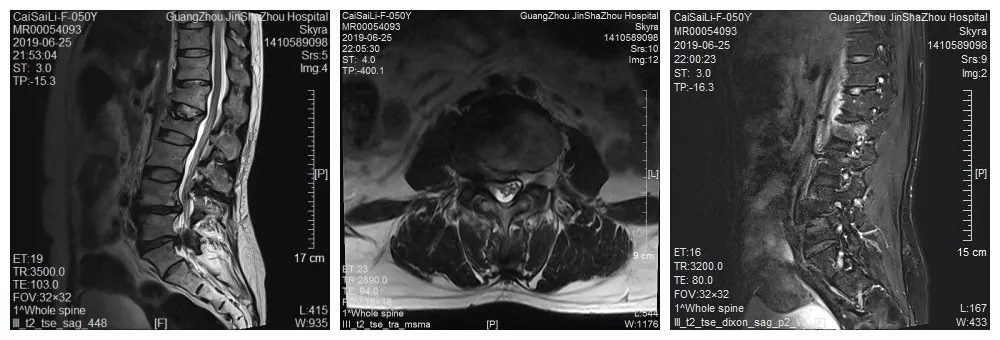

腰椎MR

于是经朋友介绍,蔡阿姨来到了我们金沙洲医院骨科中心求诊。经检查提示腰2椎体压缩性骨折,腰椎峡部裂。由于蔡阿姨的骨折和腰椎突出情况比较复杂,经过对蔡阿姨病情的详细评估,骨科中心分二次给蔡阿姨进行了手术。在我们见到蔡阿姨的时候,她第二次手术已经结束,除了下肢尚有一点点麻痹,医生说她其他方面恢复得很好,她看起来精神也不错。